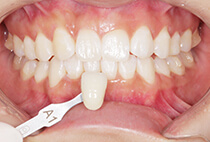

出っ歯と前歯のガタつきにお悩みだった20代女性の症例です。

金属アレルギーがあるため、メタルフリーで治療できる【インビザライン】による抜歯矯正を選択されました。

前歯のガタガタ、中心のずれ、顎のずれ、外科矯正は避けたい

叢生、左右非対称咬合

20代女性

矯正治療2年6ヶ月

インビザライン、インプラントアンカー、美容治療

矯正:1,137,400円+毎月調整量:6,050円

また、気になっていたオトガイ(顎先)の左右差に対して、

を行い、フェイスラインも自然に整えました。

矯正は「歯並びを治す」だけではありません。

当院では、呼吸・噛み合わせ・顔貌バランス・美容までトータルに整える顎顔面治療を行っています。